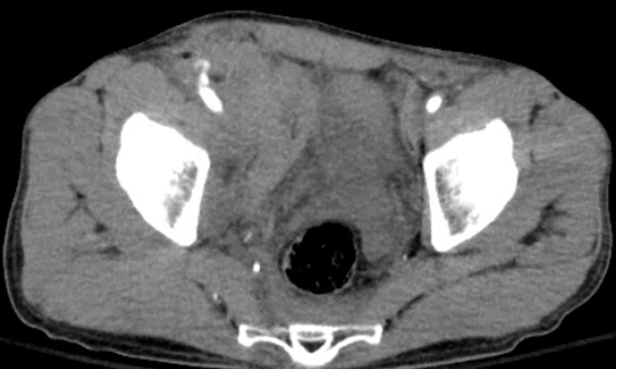

A 58 yo M develops abdominal pain and hypotension 12 hours following stent placement to the L common iliac and L superficial femoral artery for limb ischemia. Both common femoral arteries were accessed during the procedure. A CT is obtained. What's the diagnosis? (scroll down for answer)

Answer: Active extravasation from R iliac artery w/ large retroperitoneal hematoma